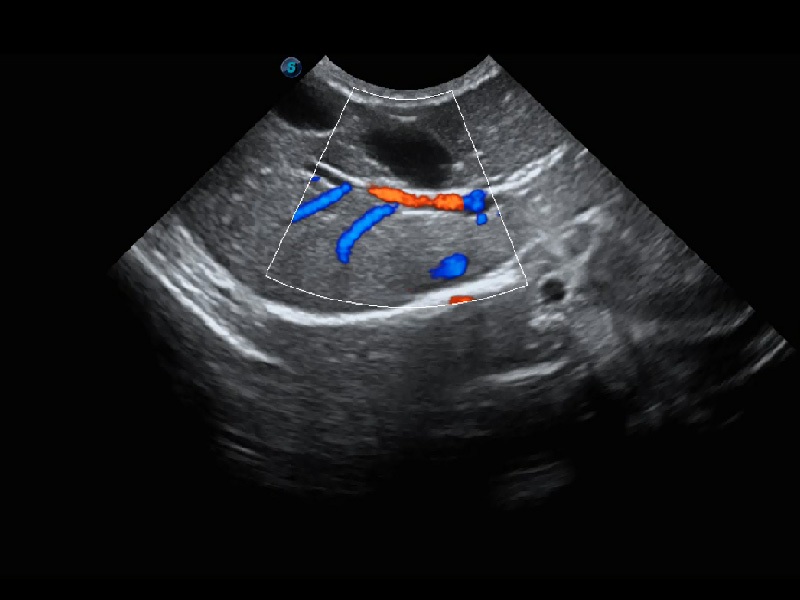

ProPet 60 作为一款高端台式动物超声设备,为动物医生的日常诊断提供了一系列贴合动物临床需求、解决临床实际问题的高级成像功能。凭借全系列高清探头,满足医生对腹部、心脏、生殖、浅表、肌骨等成像的所有需求,切实帮助您提升检查效率,提高诊断信心。

动物是人类最亲密的朋友和最值得信赖的伙伴。哈哈体育官网也一直致力于探索动物专用的超声影像解决方案。 全新推出的ProPet系列,是哈哈体育官网在动物超声影像智能化、专业化、精准化的一次跨越式革新。动物不能用言语来表述自己的不适,通过超声影像,ProPet系列搭建了动物医生与不同物种沟通的“桥梁”,为动物医生注入了“治愈之力”。